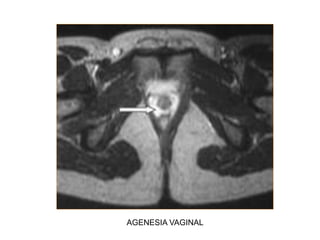

Agenesia e Hipoplasia

 5-10 %

 Fallo temprano en el desarrollo embrionario

 El Síndrome de Mayer-Rokitansky es la

malformación clase I más frecuente.

 Agenesia vaginal completa

 Agenesia uterina en el 90% de los casos

 Útero rudimentario en el 10% restante

 Se presenta con amenorrea en pacientes con

características sexuales secundarias

presentes, pues la función ovárica es normal

AGENESIA VAGINAL